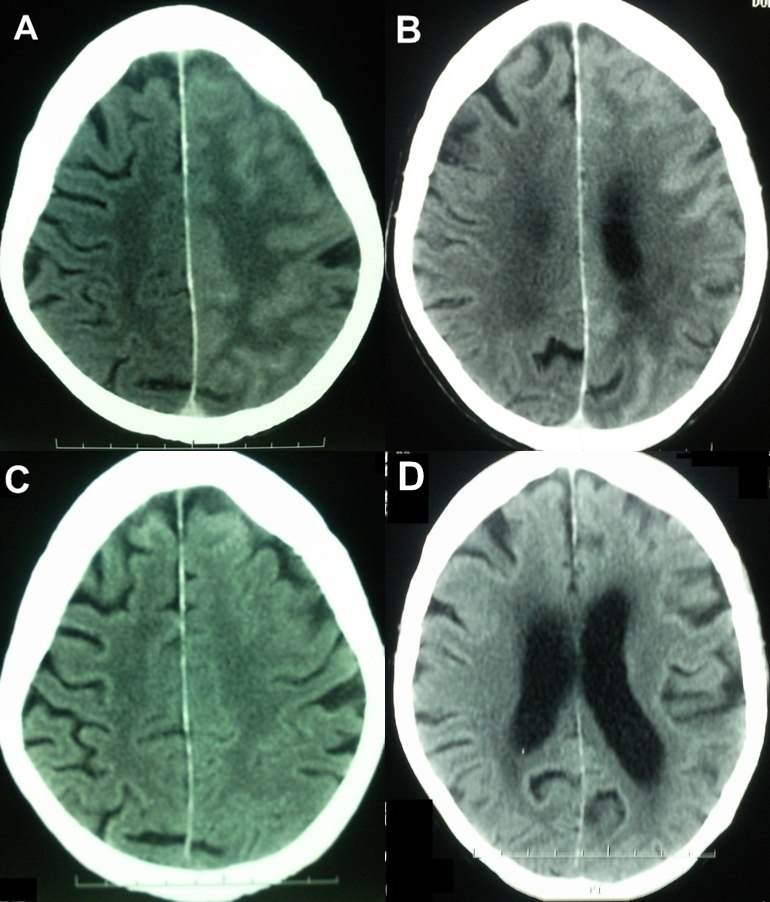

Linfoma cerebral primario y formas radiológicas atípicas